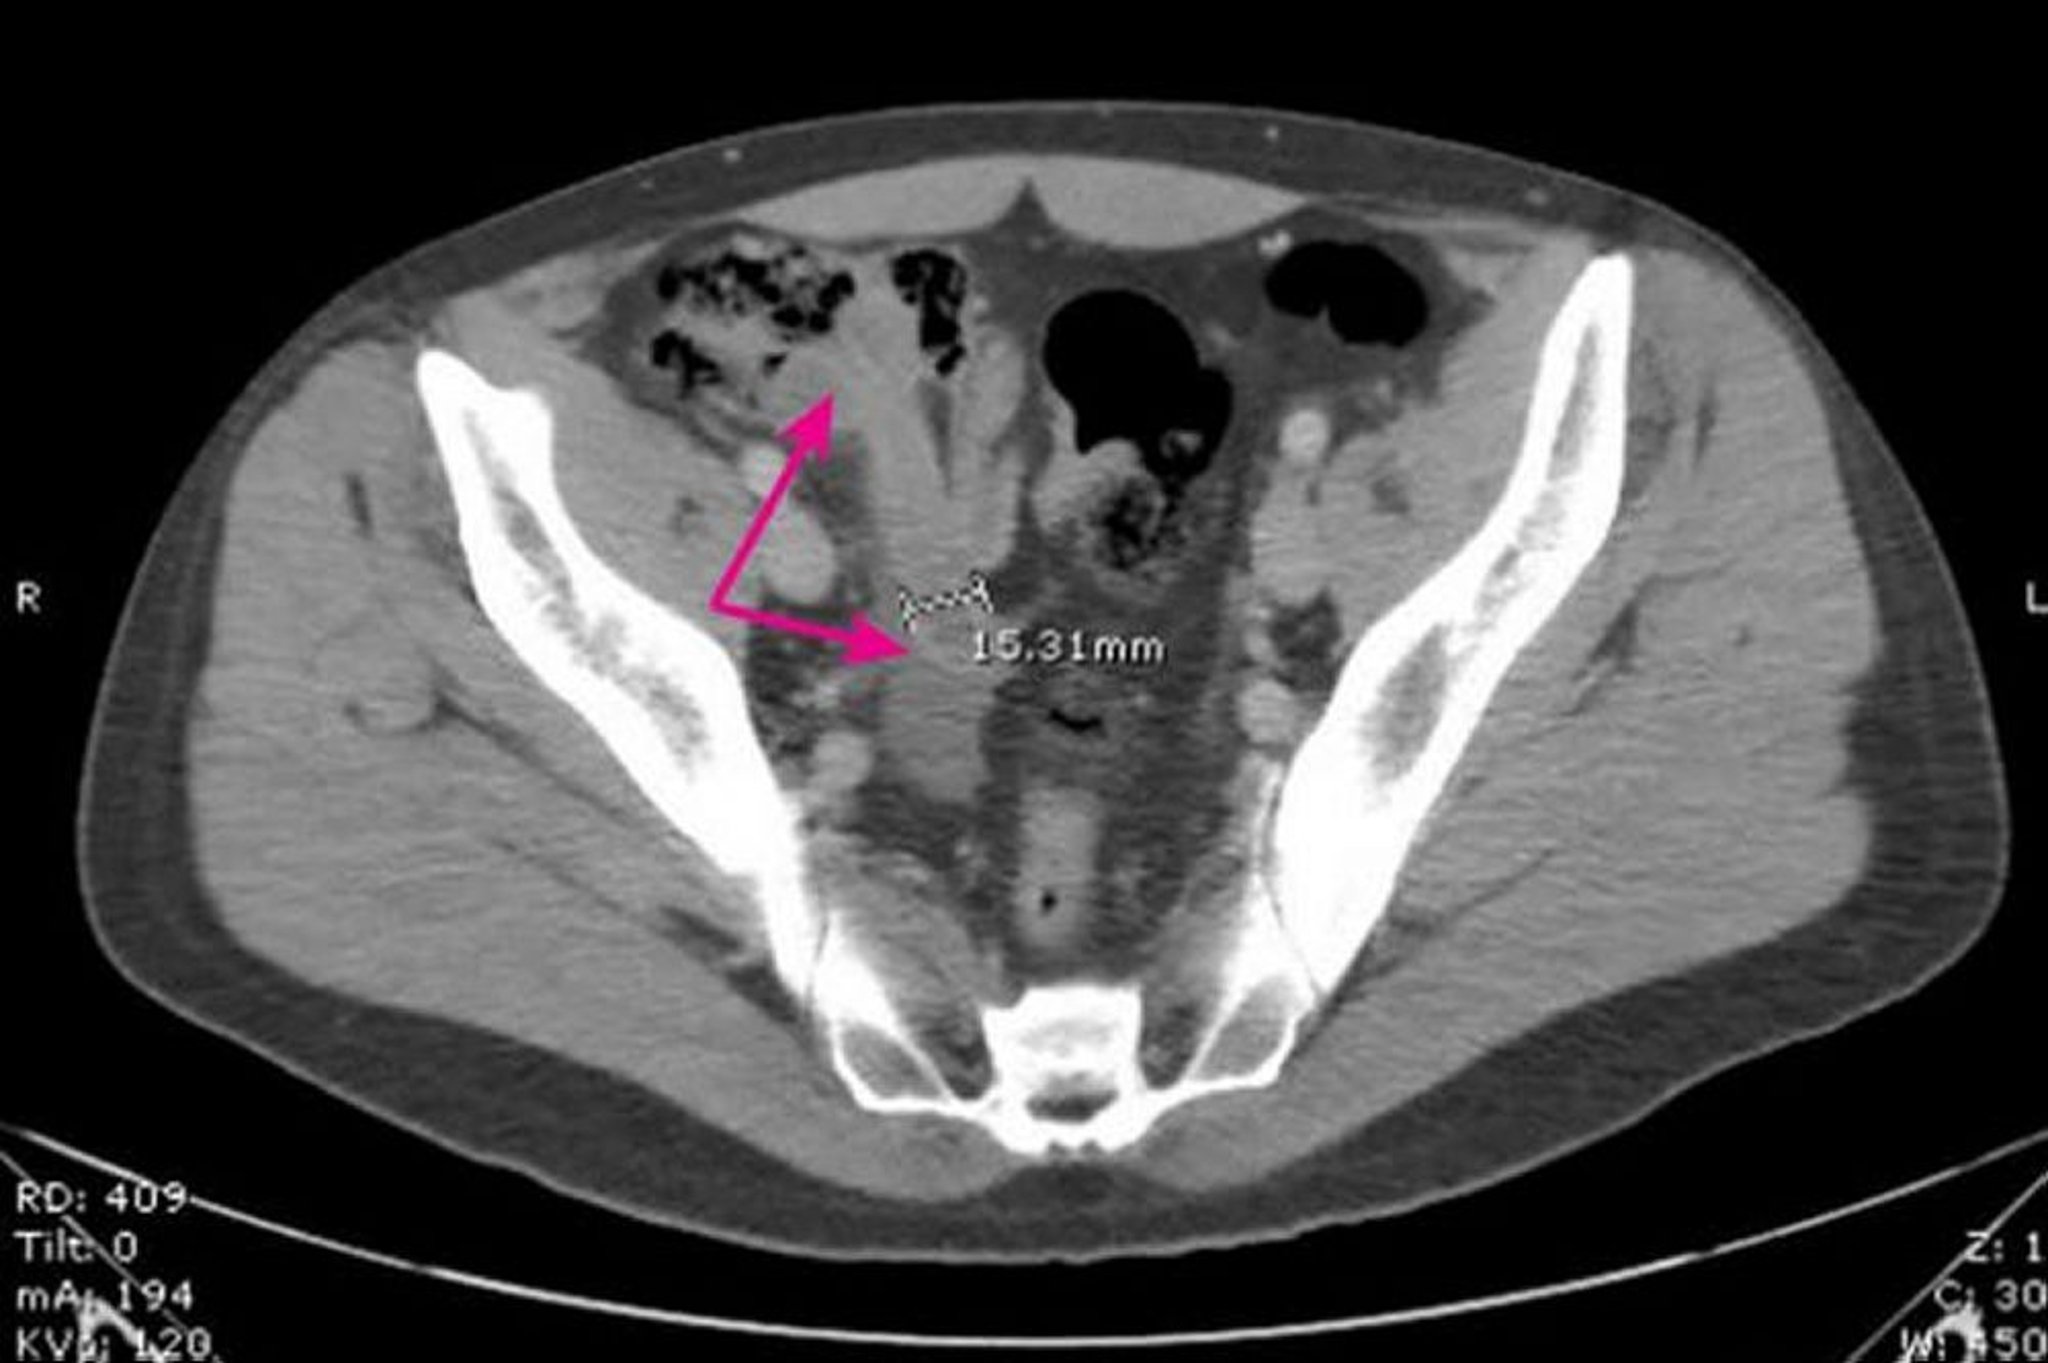

На этом изображении показан расширенный толстостенный аппендикс (стрелки) диаметром 15.31 мм с окружающими воспалительными изменениями.

Image provided by Parswa Ansari, MD.